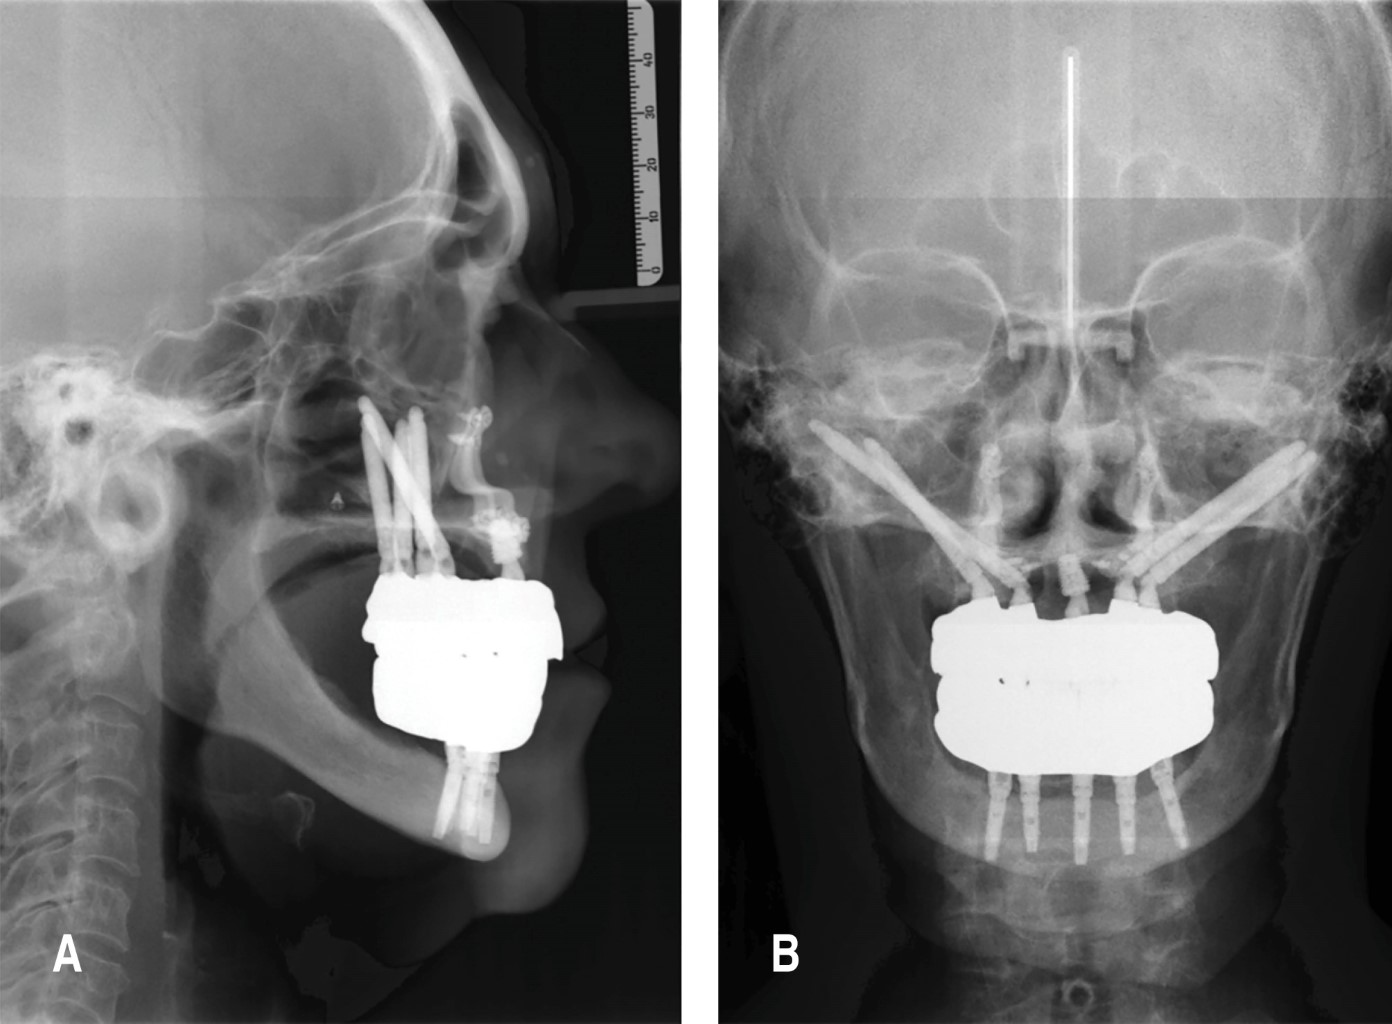

A los tres meses de la intervención, se realizan las prótesis definitivas.

RESULTADOS

En total se realizaron seis osteotomías Le Fort I, se colocaron 18 implantes cigomáticos y 55 implantes dentales convencionales entre maxila y mandíbula, además de cinco ritidectomías, 12 prótesis fijas atornilladas sobre los implantes tipo Toronto FP3 en todos los casos. Los materiales de la rehabilitación fueron prótesis hibridas de barra de titanio y acrílico, así como prótesis hibridas en zirconio. Durante el tratamiento se registró la pérdida de tres implantes dentales convencionales y un sólo implante cigomático no tuvo estabilidad primaria al momento de la colocación, por lo que se decide no colocarlo. Los implantes restantes que fallaron lo hicieron durante el tiempo de uso de las prótesis provisionales, en los primeros tres meses, y ninguno fue sustituido por no modificar el proyecto y diseño de la rehabilitación bucomaxilofacial. La tasa de éxito de los implantes dentales y cigomáticos se expone en la Tabla 1. Lo anterior coincide con las tasas de éxito en la literatura científica referida a implantología. Las prótesis provisionales fueron aplicadas a los 10 días postquirúrgicos, después del retiro de suturas; los provisionales se rebasaron progresivamente. Después de tres meses se realiza la toma de registros para la confección de la prótesis definitiva, concertando la nueva relación maxilomandibular y planificando acorde su rehabilitación (Figura 7). Se realiza la entrega de las prótesis definitivas. En un caso se reportó la fractura de componentes acrílicos de la restauración y un paciente presentó el aflojamiento de tres tornillos. En ambos casos se realizaron los arreglos pertinentes y se continuó sin eventualidades (Figura 8). Se solicita al paciente, una vez entregada la rehabilitación fija, que asista a citas periódicas para higiene profesional cada tres meses durante el primer año de seguimiento. Durante la primera consulta de higiene, se le entrega una encuesta para determinar el nivel de satisfacción con el tratamiento y las mejoras subjetivas en su calidad de vida. En pacientes con antecedentes de SAHOS, se les pide llenar el índice de calidad de sueño de Pittsburgh (PSQI) y tener un parámetro de mejoría en su condición después del tratamiento. En todos los casos, las respuestas de los pacientes fueron sumamente positivas en relación con la mejora en calidad de vida, sueño y bienestar general (Tabla 2). Los pacientes calificaron su grado de satisfacción en una escala estandarizada. Las áreas de evaluación incluyeron mejoras en la función masticatoria, la claridad del habla, la deglución, la respiración durante el sueño y la estética facial. Una puntuación más alta indica una mayor satisfacción y, por lo tanto, una mejora significativa en esa área específica de la calidad de vida.